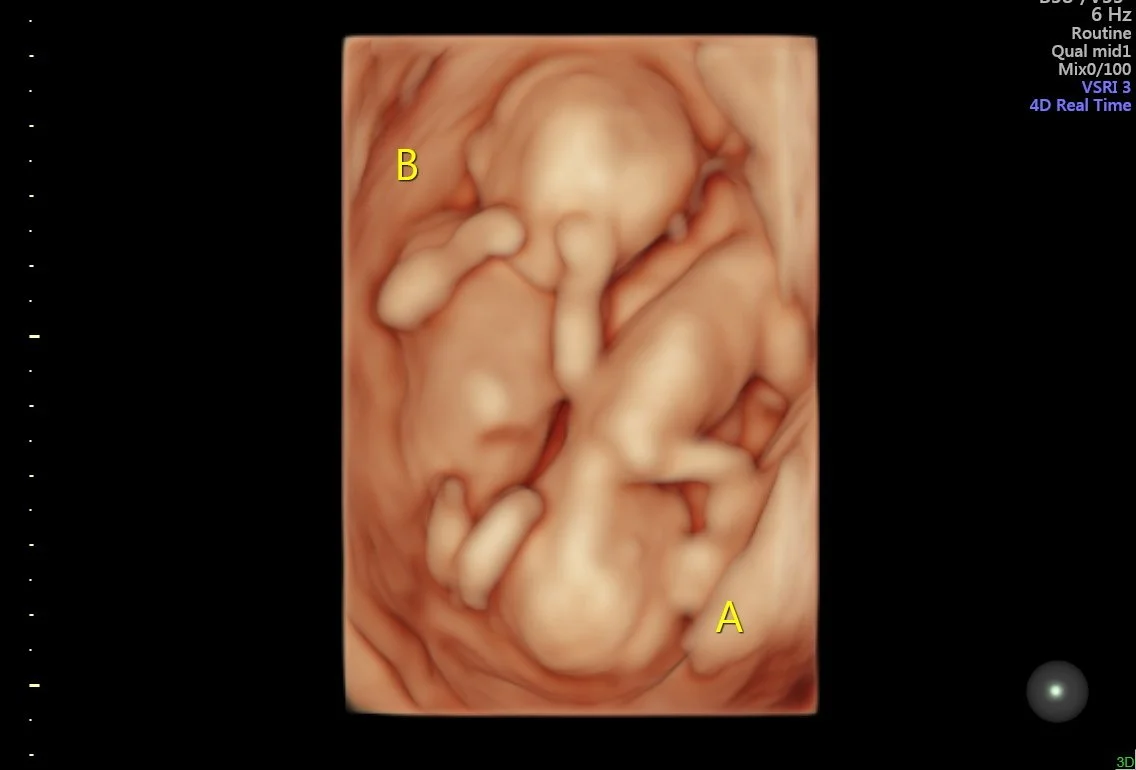

Our state of the art technology allows us to see your baby in a whole different way! With HD Live imaging, we can watch your baby wiggle, smile and yawn all in real time!